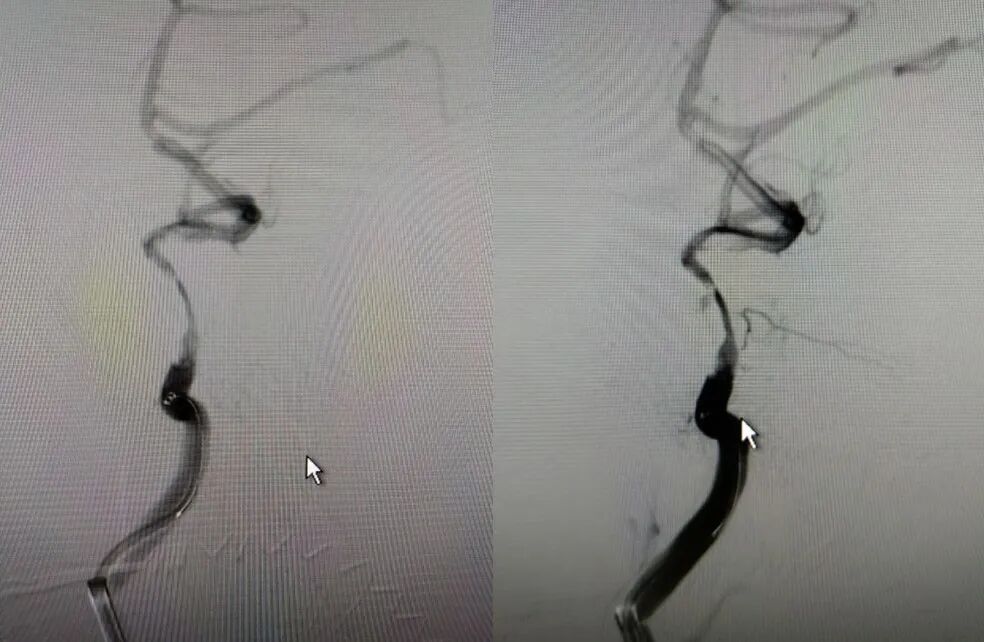

治疗中影像

Guiding到位,导丝通过病变。

导丝怎么扩【载药时代 球扩天下】NOVA DES®颅内药物洗脱支架在大脑中动脉重度狭窄的应用二例!_https://www.jmylbn.com_新闻资讯_第24张

球囊通过病变。

导丝怎么扩【载药时代 球扩天下】NOVA DES®颅内药物洗脱支架在大脑中动脉重度狭窄的应用二例!_https://www.jmylbn.com_新闻资讯_第25张

球囊扩张过程。

导丝怎么扩【载药时代 球扩天下】NOVA DES®颅内药物洗脱支架在大脑中动脉重度狭窄的应用二例!_https://www.jmylbn.com_新闻资讯_第26张

扩张后造影。

导丝怎么扩【载药时代 球扩天下】NOVA DES®颅内药物洗脱支架在大脑中动脉重度狭窄的应用二例!_https://www.jmylbn.com_新闻资讯_第27张

支架通过病变。

导丝怎么扩【载药时代 球扩天下】NOVA DES®颅内药物洗脱支架在大脑中动脉重度狭窄的应用二例!_https://www.jmylbn.com_新闻资讯_第28张

支架释放。

导丝怎么扩【载药时代 球扩天下】NOVA DES®颅内药物洗脱支架在大脑中动脉重度狭窄的应用二例!_https://www.jmylbn.com_新闻资讯_第29张